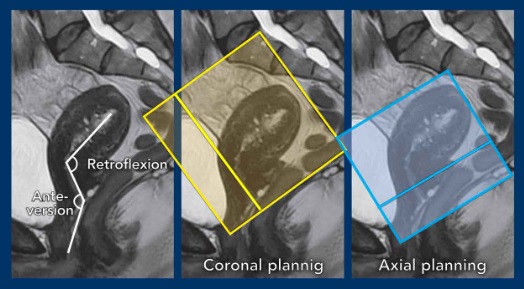

Example showing how flexion, and in particular version impact sequence planning.

- In this case there is anteversion of the cervix and retroflexion of the uterus.

- Remember that in cervical cancer, the axial sequences are planned perpendicular to the cervical canal.

Another example showing the cervix in retroversion and the uterus in anteflexion.

See how this variation in position impacts the corresponding sequence planning.